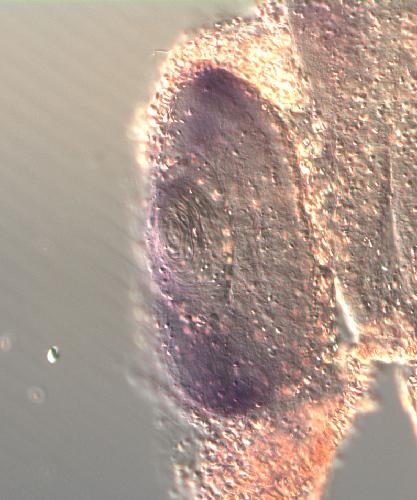

???displayGene.symbol???: dnajc5

???displayGene.name???: DnaJ heat shock protein family (Hsp40) member C5

May have an important role in presynaptic function. May be involved in calcium-dependent neurotransmitter release at nerve endings.

Diseases: Disease Ontology: neuronal ceroid lipofuscinosis 4

CEROID LIPOFUSCINOSIS, NEURONAL, 4 (KUFS TYPE); CLN4